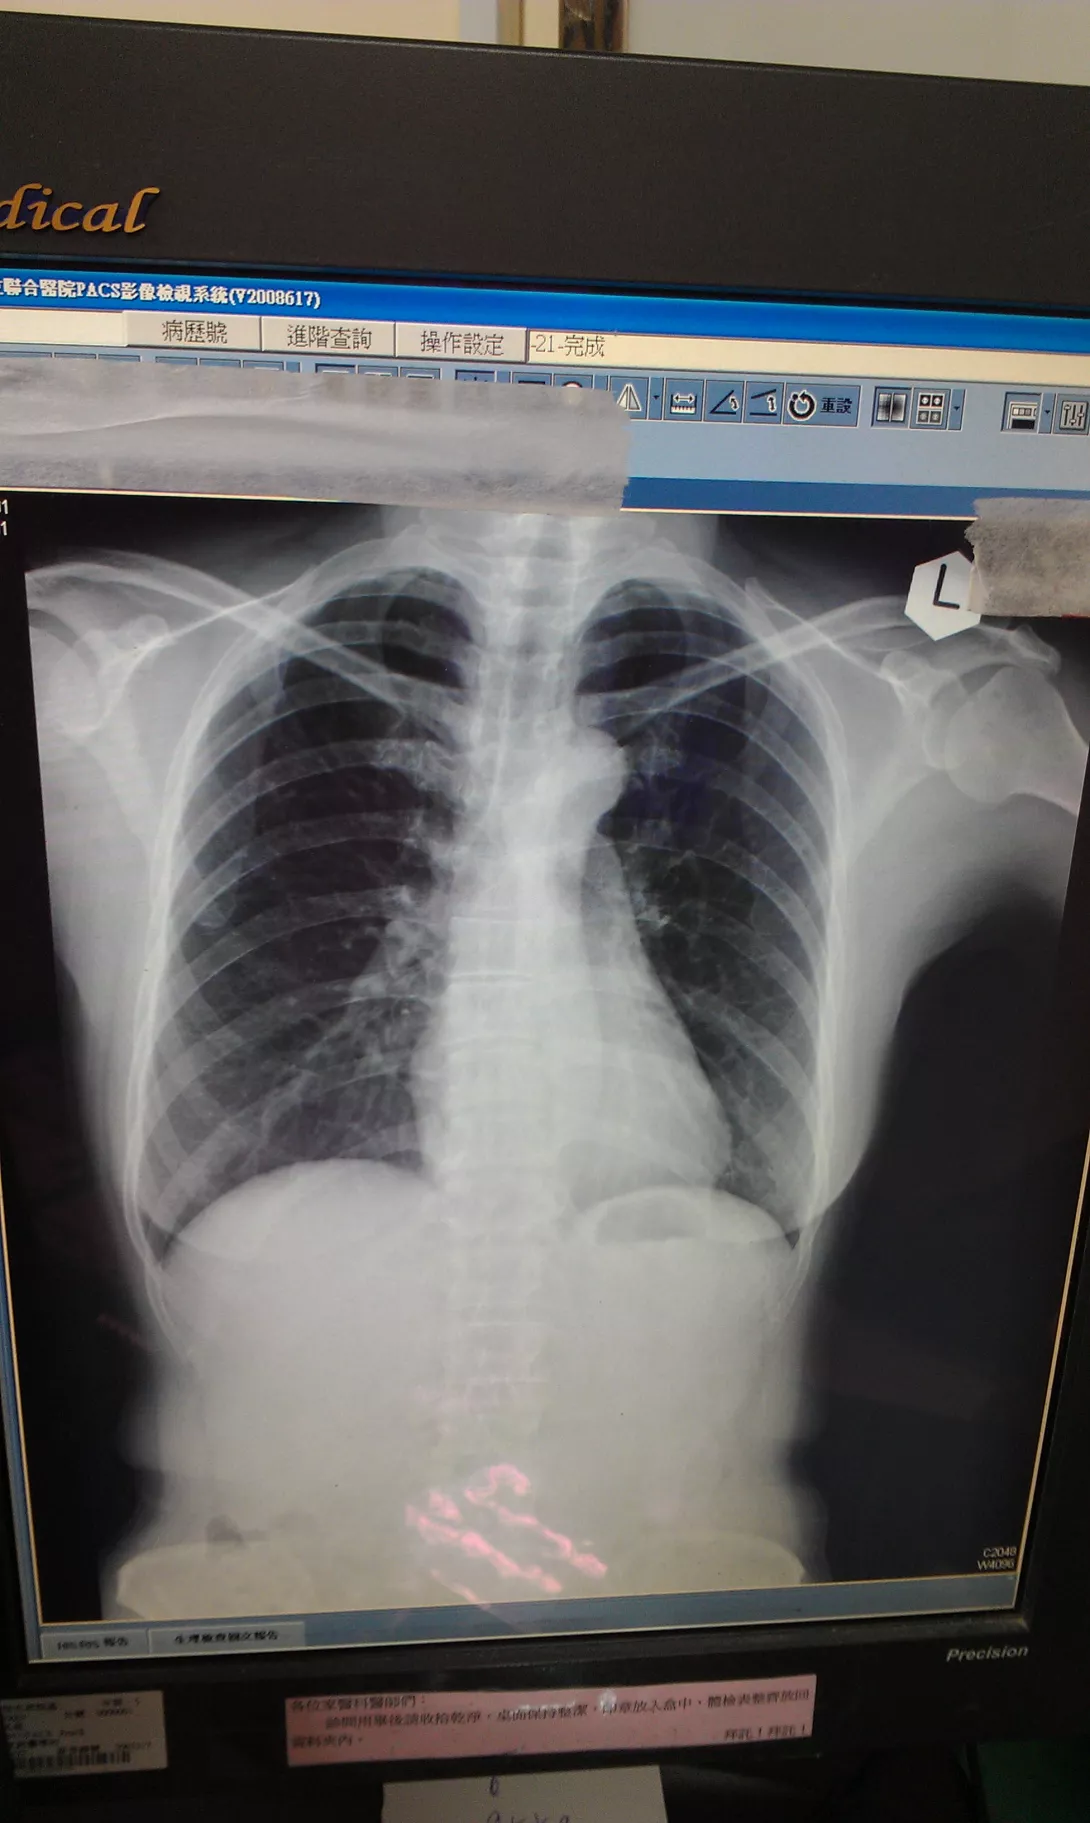

醫生說我的胸椎和腰椎有很多骨刺,但我還沒弄清骨刺該如何看?

之前兩年前的電光照片,很明顯有側彎,不過醫生認為年紀大了自然會有些問題,不必太掛慮。但以中醫上醫治未病的理念,還是要處理才是王道。很高興自己用自然療法,解決此問題。